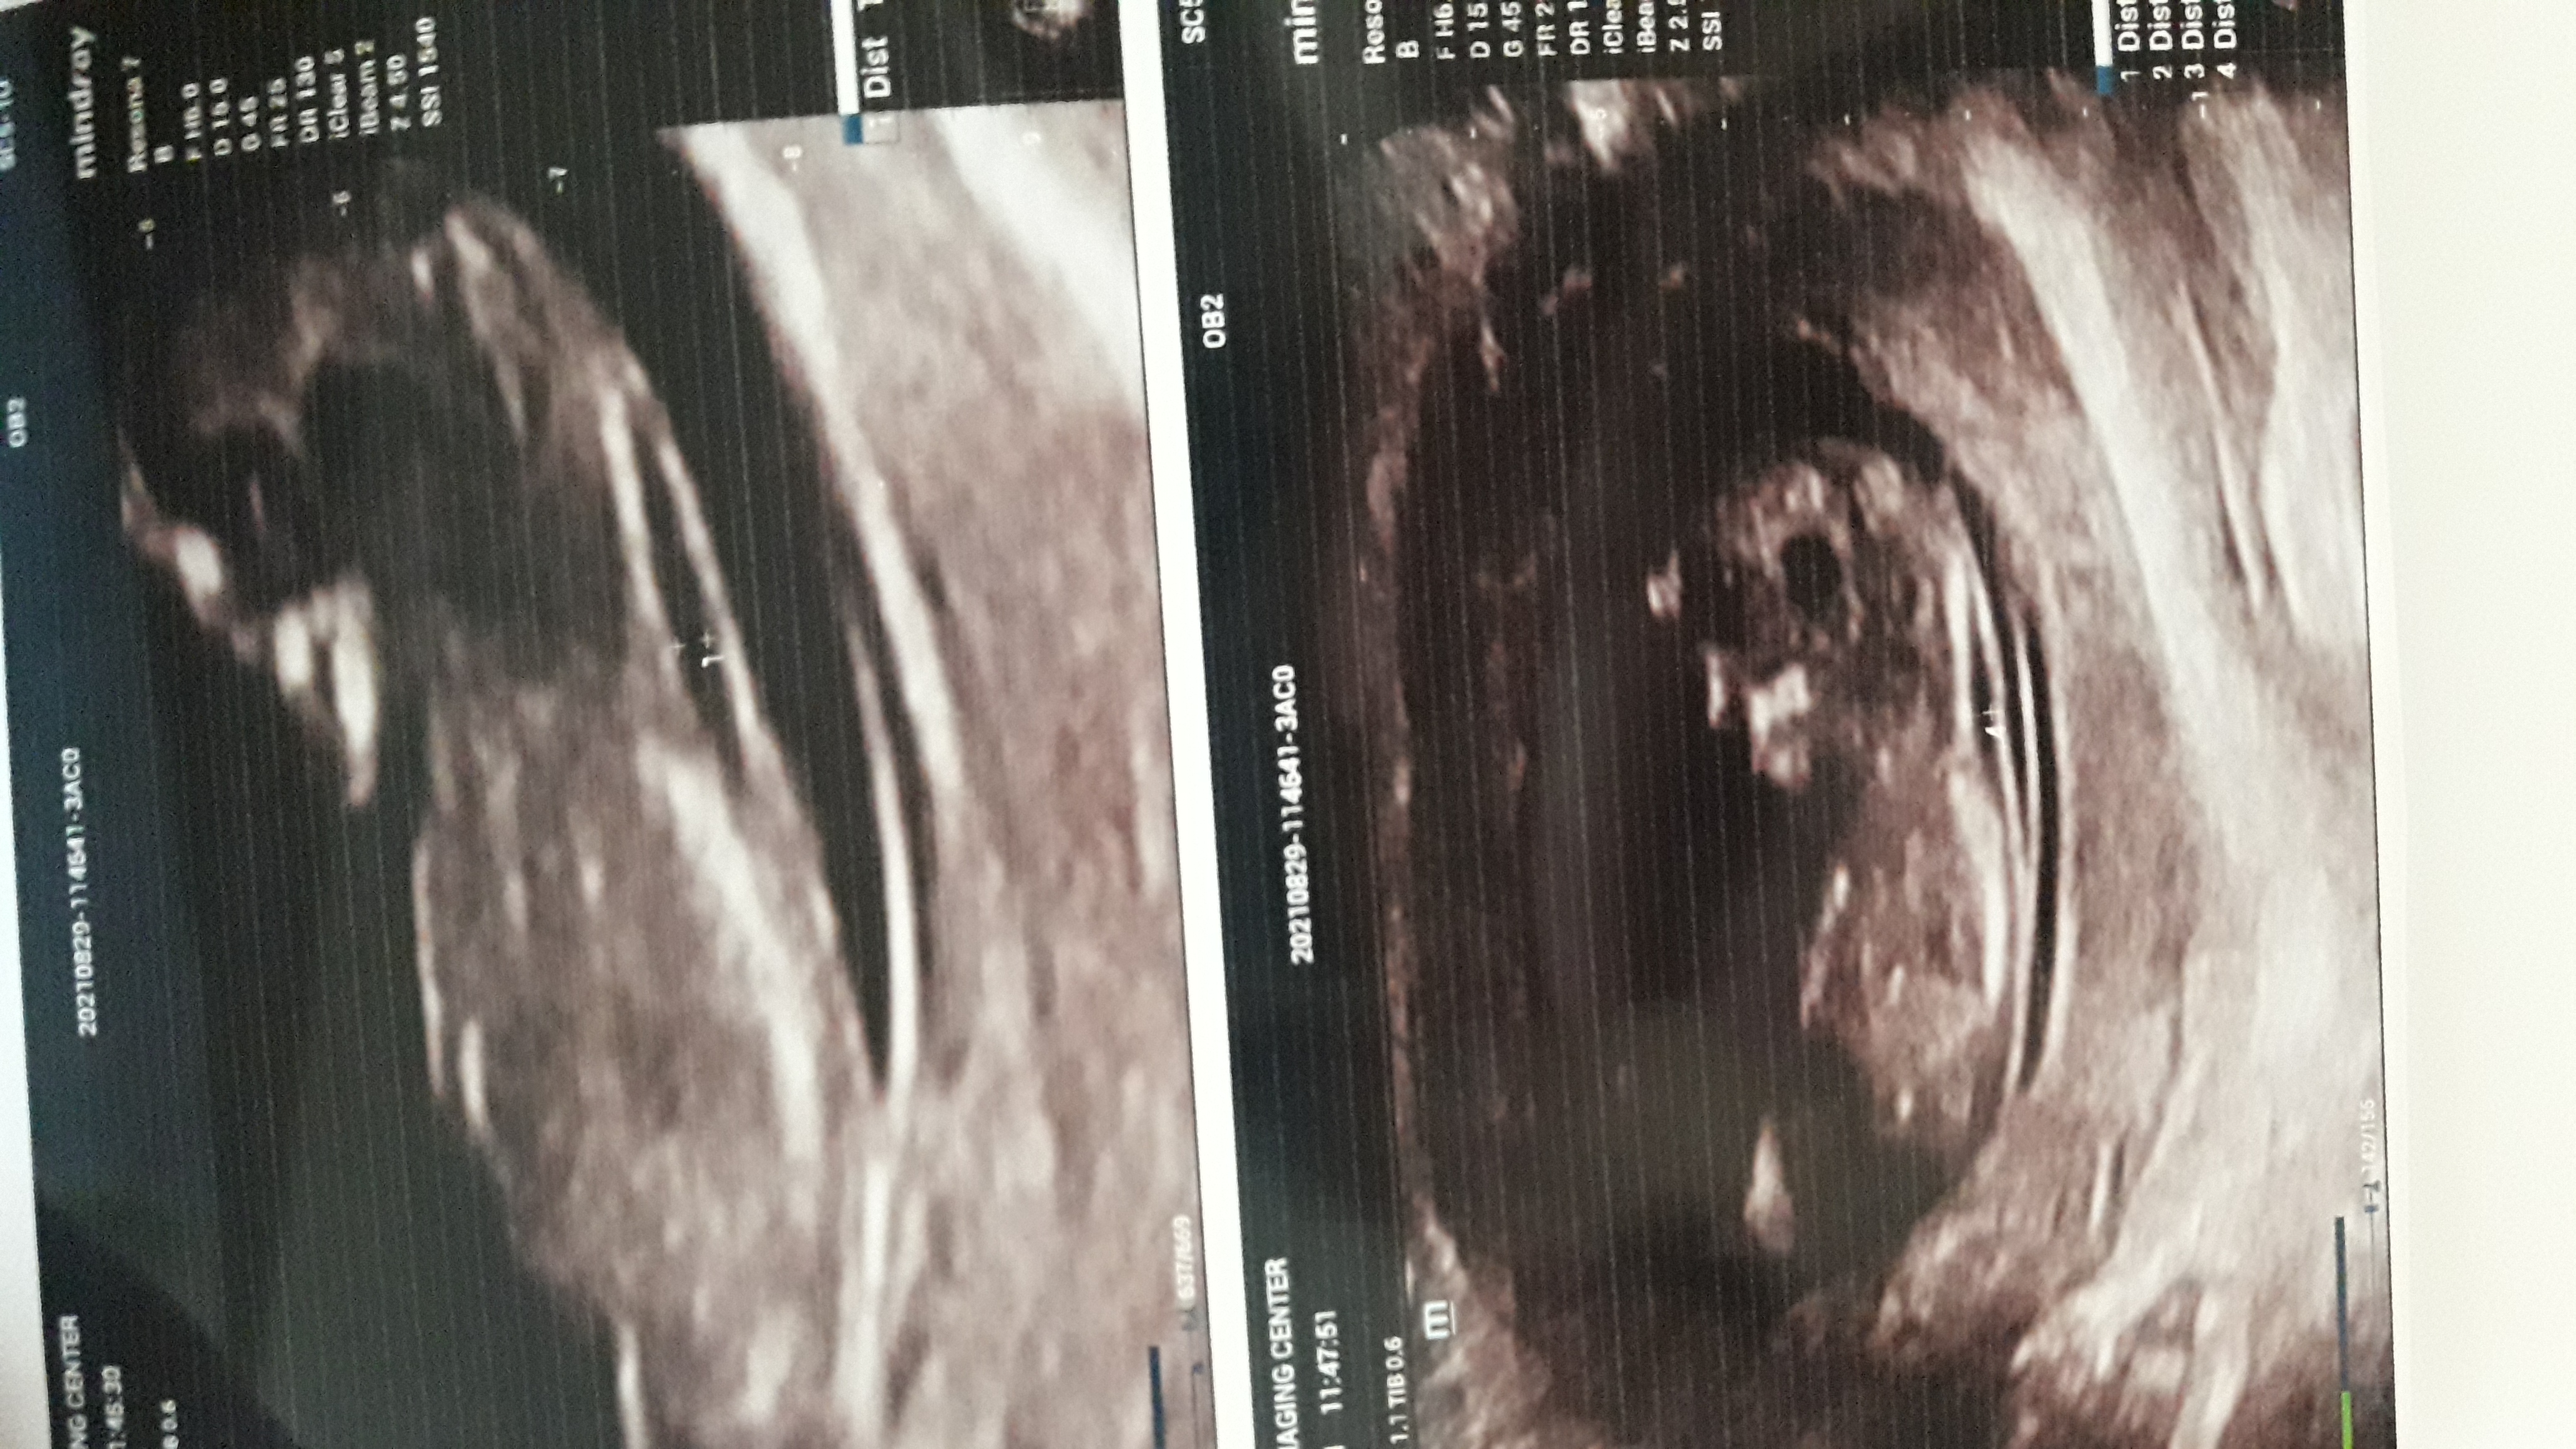

قاصدک این‌عکسش رو ببین

سلام عزیززدل.. ممنون میشم ب منمجواب بدی این دوتا عکس مربوط ب سونو ان تی دوازده هفته و جهارروز من هست میخواستم ببینم میتونی تشخیص بدی عکس بالایی رو از روی فیلم گرفتم پایینی عکس سونو هس یکم واضح نیست ممنونم

سلام عزیززدل.. ممنون میشم ب منمجواب بدی این دوتا عکس مربوط ب سونو ان تی دوازده هفته و جهارروز من هست ...

عکست واضح نیست اما اونی که  تو عکست میبینم طبق نظریه ناب دختره

تو عکست مشخص میکنم نگاه کن

ولی جدا از تصویر دنبالچه من شدیداً حس میکنم حالت هاش پسرونه است و پسره

عکست واضح نیست اما اونی که  تو عکست میبینم طبق نظریه ناب دختره  تو عکست مشخص میکنم ن ...

مرسی عزیزم ممنونم ازت البته سونو ان هم باتردید گفت دختر... اما ی کوچولو دوس دارم نینی اولم پسر باشه بازم هرچی خدابخپاد